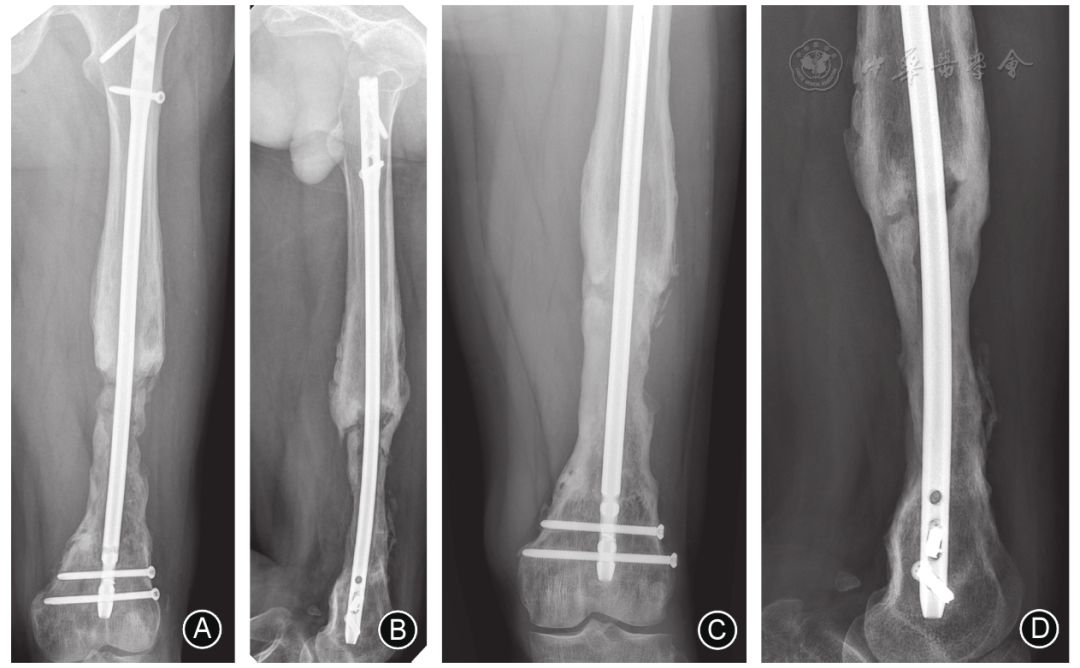

图7 膜诱导重建过程中发生骨延迟愈合,可行负重训练,其中一部分患者可在骨移植术后1~2年缓慢愈合 A,B 膜诱导重建术后1年正、侧位X线片示植骨区成骨不全,近端发生骨不连 C,D 术后2年,正、侧位X线片示移植骨塑形良好